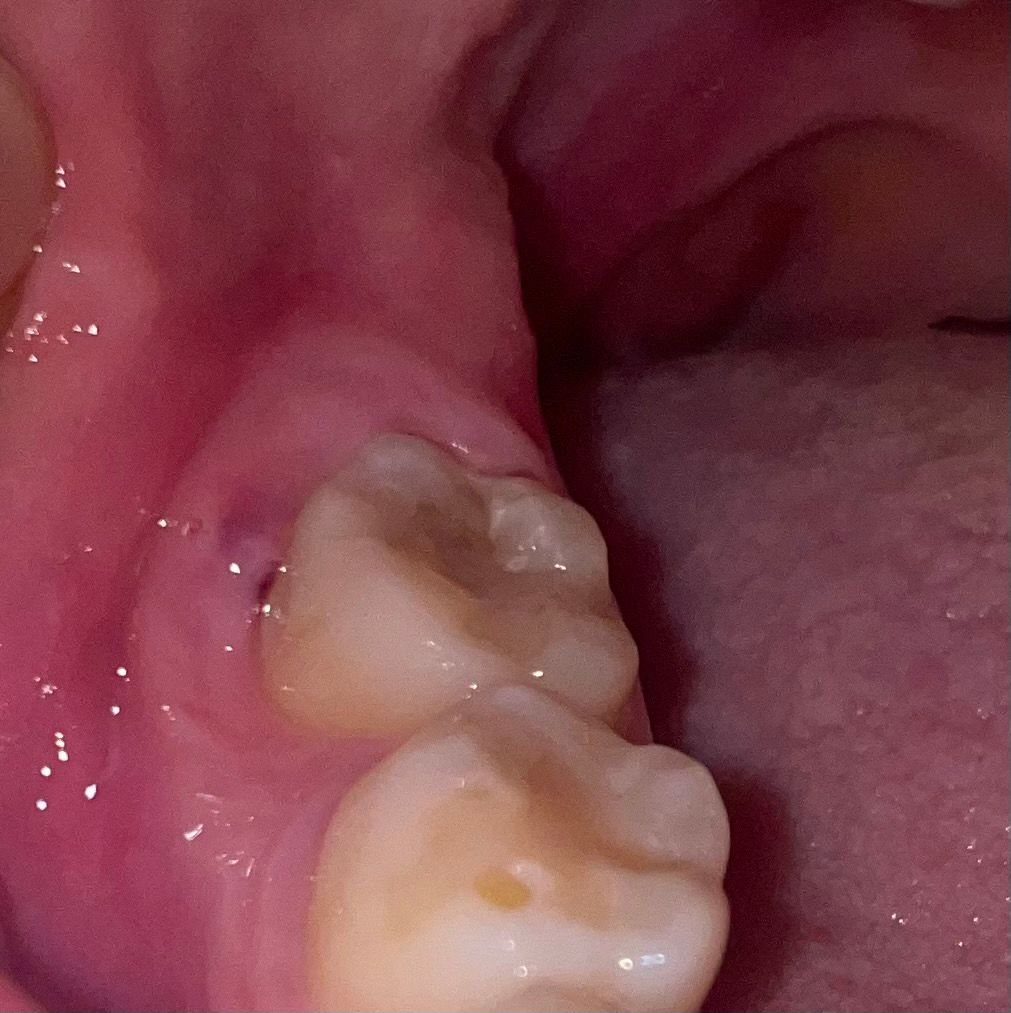

맨 끝 치아가 아파요.. 이거 뭔가요..?

이게 뭔가요???

1. 붓고 피도 나는 것 같은데 이게 뭔가요? 뭔가가 이물질이 틈으로 박힌건가요..?

2. 사랑니인가요..? 그런데

사랑니가 옆으로 자라는 것도 아닌데, 치아 뒤가 아니라 치아 옆이 저렇게 부을 수가 있는건가요?

• 1번 째 사진